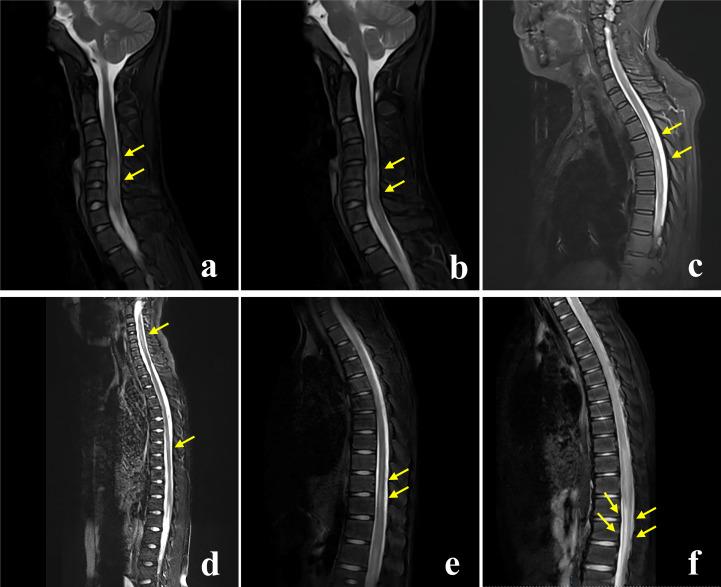

RESULTS

Out of 59 patients, 18 were children (under 18 years old), and 31 were adults. The overall cohort's median age at onset was 32 years old, 7 for children, and 42 for adults. There were 23 (41.1%) patients with prodromic infection, 1 (1.7%) patient with a tumor, 29 (53.7%) patients with other non-neurological autoimmune diseases, and 17 (22.8%) patients with hyponatremia. Fourteen (23.7%) patients had multiple neural autoantibodies, with the AQP4 antibody being the most common. Encephalitis (30.5%) was the most common phenotypic syndrome. Common clinical symptoms included fever (59.3%), headache (47.5%), nausea and vomiting (35.6%), limb weakness (35.6%), and disturbance of consciousness (33.9%). Brain MRI lesions were primarily located in the cortex/subcortex (37.3%), brainstem (27.1%), thalamus (23.7%), and basal ganglia (22.0%). Spinal cord MRI lesions often involved the cervical and thoracic spinal cord. There was no statistically significant difference in the MRI lesion site between children and adults. Out of 58 patients, 47 (81.0%) had a monophasic course, and 4 died. The last follow-up showed that 41/58 (80.7%) patients had an improved functional outcome (mRS <3), and children were more likely than adults to have no residual disability symptoms (p = 0.001).